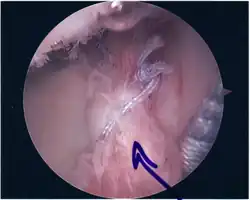

SLAP Tear

Repair of SLAP Tear

Arthroscopic SLAP Lesion (type 2) repair

Following inspection and determination of the extent of injury, the basic labrum repair is as follows.

• The glenoid and labrum are roughened to increase contact surface area and promote re-growth.

• Locations for the bone anchors are selected based on number and severity of tear. A severe tear involving both SLAP and Bankart lesions may require seven anchors. Simple tears may only require one.

• The glenoid is drilled for the anchor implantation.

• Anchors are inserted in the glenoid.

• The suture component of the implant is tied through the labrum and knotted such that the labrum is in tight contact with the glenoid surface.